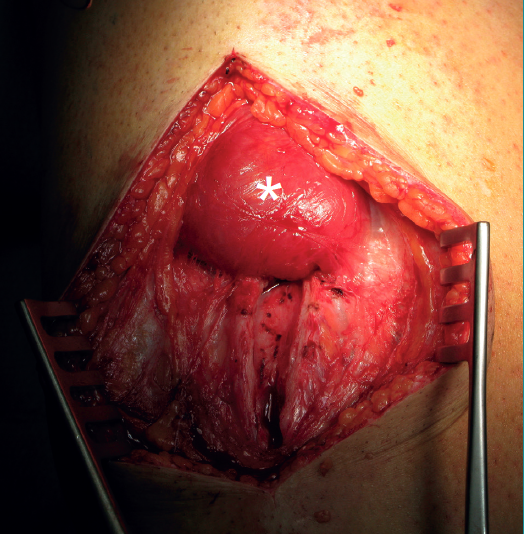

Indirect injuries of the rectus femoris are frequent, in the same way as direct injuries of the vastus medialis and vastus lateralis. Direct injuries are frequent in team sports such as football, rugby or American football, and also in combat sports such as kick-boxing, and usually produce important pain. The ultrasound and magnetic resonance imaging (MRI) studies evidence great destructuring of the muscle tissue, though there is often a surprising dissociation with respect to the clinical manifestations - athletes often being able to continue their sports activities with only minimal limitation despite the lesion(4). Sometimes, and particularly in the occupation setting, we can encounter serious injuries, with muscle sectioning secondary to direct traumatisms, that may require surgical treatment (Figure 1).

Figure 1. Right thigh. The head is to the left of the image. Complete sectioning of the vastus medialis, rectus femoris and vastus intermedius caused by the fall of a blunt and very heavy object (the edge of a metal door, from a height), with the knee flexed. Surgical approach for suturing the different muscle bellies.